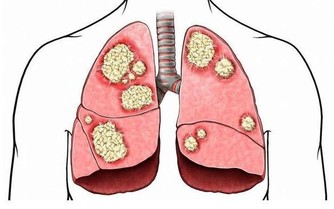

俗話說“是藥三分毒”,藥沒吃對,肝臟受罪。如今新冠肺炎疫情尚未結束,不少人希望通過吃一些藥方來預防疫情,但這真的沒有必要。

國家衛生健康委專家組成員張伯禮早前接受采訪曾表示,不主張人人吃中藥來預防。最近炒得比較熱的雙黃連,也只是清熱解毒的一類中藥,比較偏寒,不適合一般人服用。

建議:藥物務必遵照醫囑和說明書服用,切忌亂買亂吃。